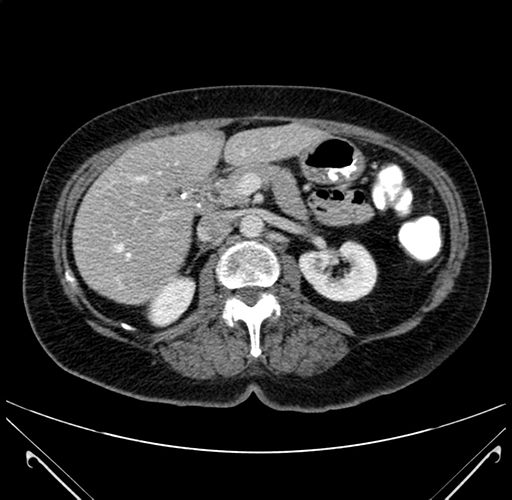

Axial Venous

Imaging analysis

Based on your CT findings, which issue(s) would give reason for "planned slowing down moment(s)" in this case?

Considering a standard right hepatectomy procedure, what step(s) of the operation would you do differently in this case?